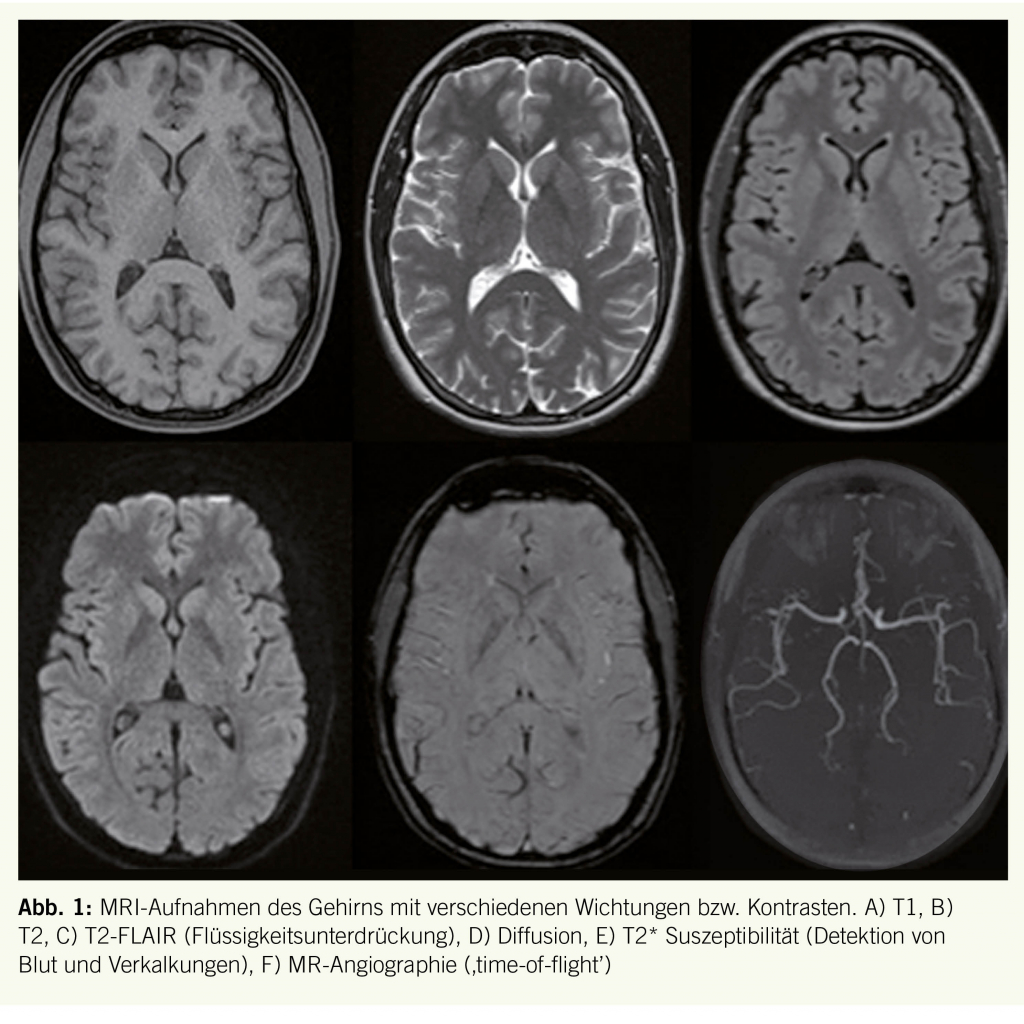

Die meisten neurologischen Fragestellungen werden heutzutage mittels MRI abgeklärt. Insbesondere für die Beurteilung der zerebralen Strukturen ist der hohe Weichteilkontrast und die Möglichkeit, mit verschiedenen Geräteparametern spezifische Kontraste zu erzeugen, ein entscheidender Faktor. Zudem liefern MRI Techniken wie die Diffusions- und Perfusionsanalyse sowie die Spektroskopie weitere Informationen auf molekularer Ebene zur Charakterisierung von gefundenen Strukturalterationen (Abb. 1).